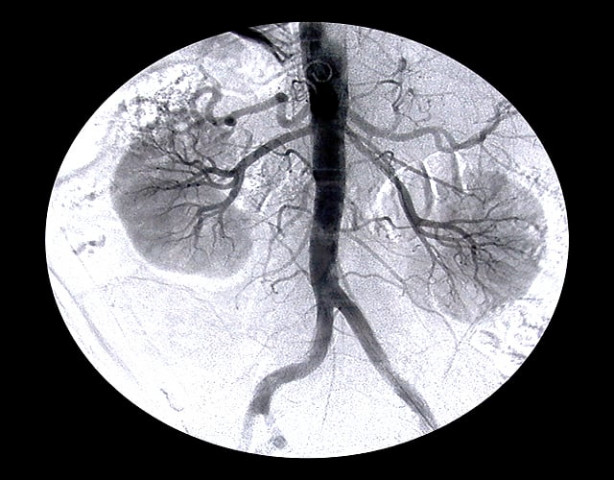

PHOTO: FILE